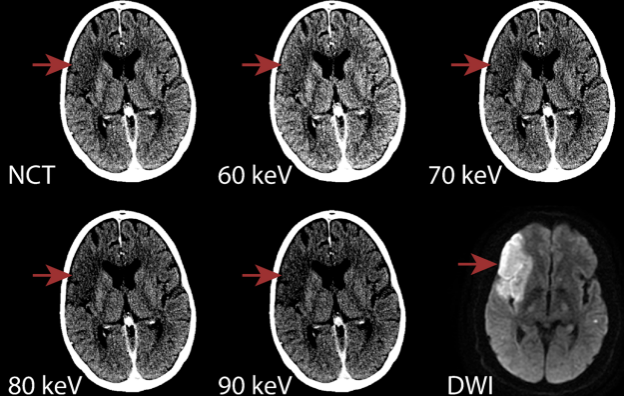

80–90keV VMI能区分正常和梗死脑实质